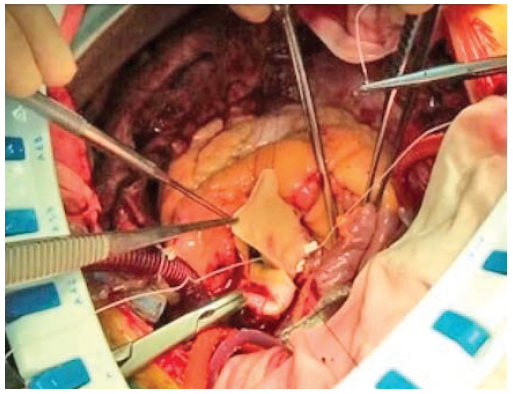

Интраоперационно аортальный клапан трехстворчатый, с выраженным кальцинозом створок. Обращает на себя внимание малый размер корня аорты. Произведено иссечение створок аортального клапана. При измерении диаметра базальное кольцо корня аорты не пропускает измеритель №19. Выполнена анну- лорасширяющая реконструкция корня аорты по методике Nicks: корень рассечен по середине некоронарного синуса до уровня базального кольца, в эту область имплантирована клиновидная заплата из ксеноперикарда (рис. 2). В позицию аортального клапана имплантирован биологический протез №21. Восстановление целостности стенки аорты произведено полипропиленовой нитью 5-0. Следующим этапом выполнены маммарокоронарное шунтирование и резекция ушка левого предсердия. Синусовый ритм восстановлен после разряда дефибриллятором.

Рис. 2. А. Корень аорты рассечен по середине некоронарного синуса до уровня базального кольца, в эту область имплантирована клиновидная заплата из ксеноперикарда.